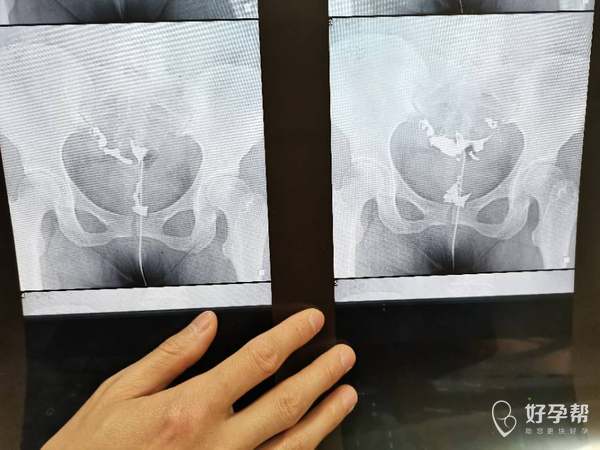

请问造影片子上能看出是输卵管哪里堵塞吗做腹腔

从片子看你这个是输卵管远端阻塞,做宫腹腔镜联合手术效果比较好